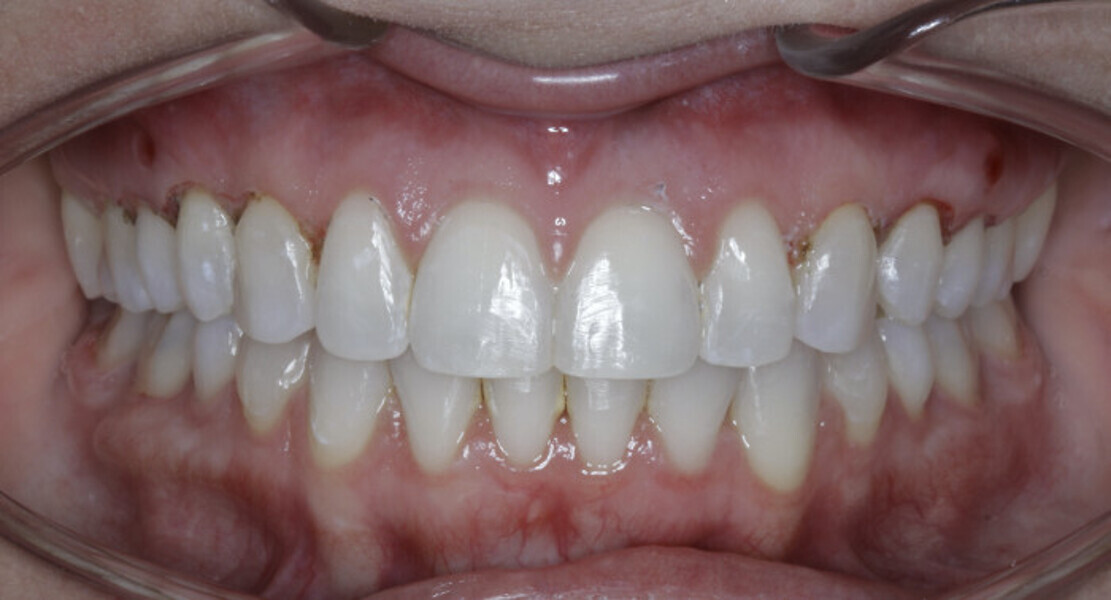

New Age orthodontics and orthopaedics with temporary anchorage devices